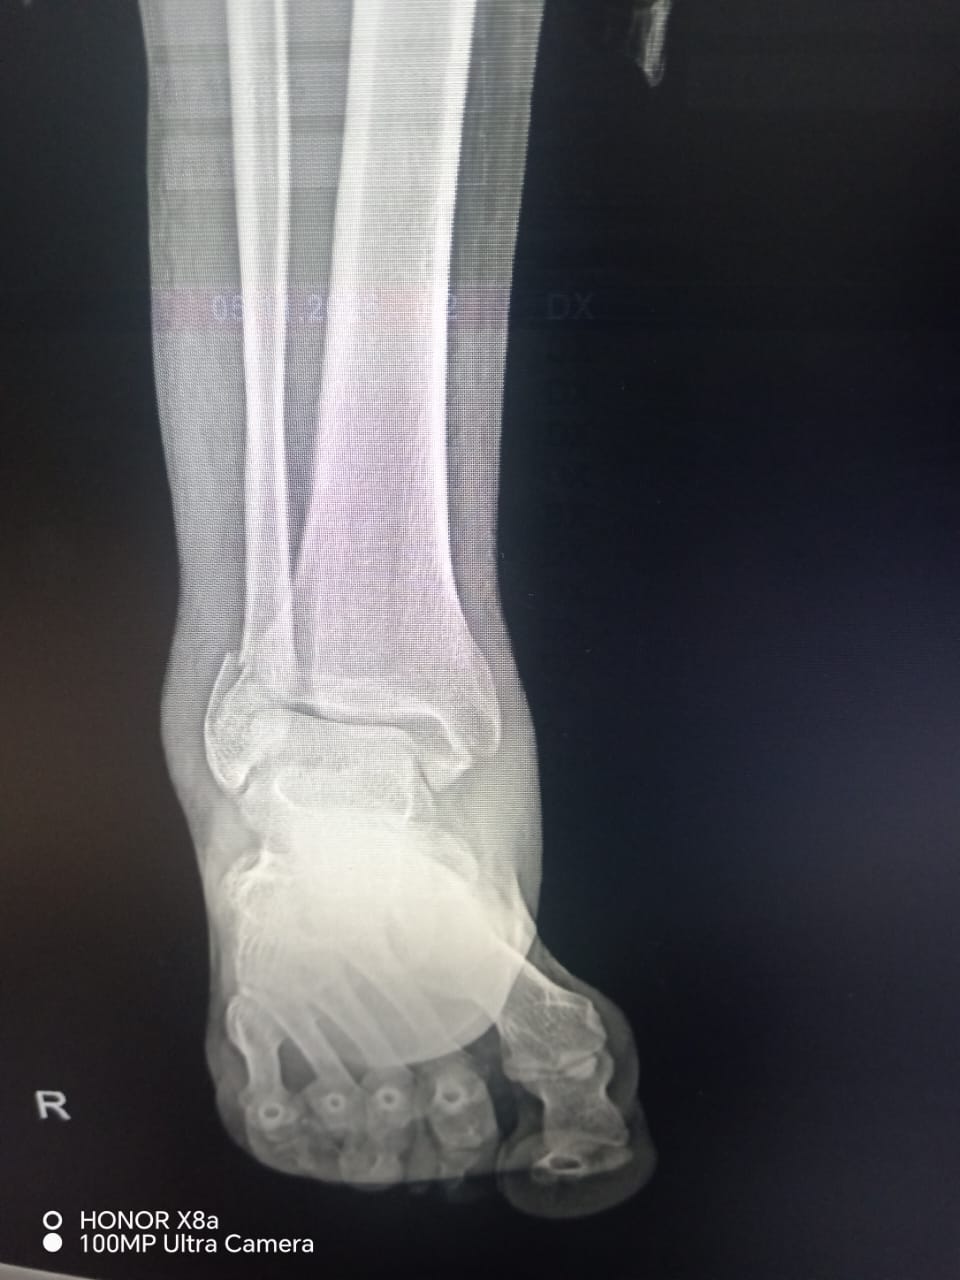

Rentgen müayinəsindən sonra vətəndaşa ayağında üç yerdən sınıq və ya qırıq olduğu bildirilərək mil (metall konstruksiya) taxılması məqsədilə əməliyyata cəlb olunub.

Məlumat üçün qeyd edək ki, vətəndaşın rentgen görüntüləri də redaksiyamıza təqdim olunub.